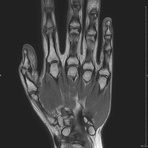

- Beurteilung von Knochen, Bändern und anderen Weichteilstrukturen der Gelenke nach Unfall.

- Arthrosediagnostik (Knorpelschaden)

- Impingement-Symptomatik

- Ursachenklärung bei wiederholter spontaner Gelenkluxation

- Ausbreitungsdiagnostik bei Gelenkentzündung, z.B. im Rahmen von rheumatischen Grunderkrankungen

- MR-Arthrographie – nach örtlicher Betäubung und gründlicher Desinfektion der Haut wird unter Lagekontrolle mit Röntgen-Durchleuchtung eine kleine Nadel in den Gelenkraum positoniert und darüber ein MR-taugliches Kontrastmittel in den Gelenkraum gespritzt. Danach wird die Nadel entfernt. Anschließend erfolgt die MRT des Gelenkes. Diese Methode stellt kleine anatomische Strukturen des Gelenkraumes verbessert dar, z.B. zur Therapieplanung vor Arthroskopie bei Sportverletzungen der Schulter oder Gelenkinstabilität.